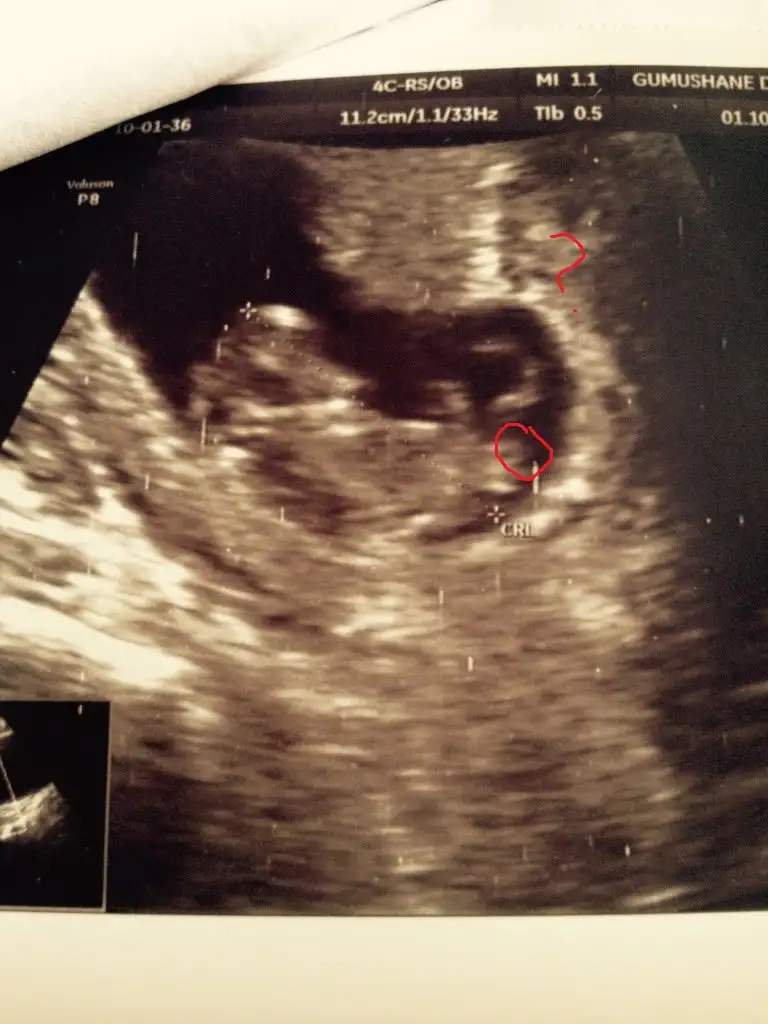

Ben anlamadim. Benimki Erkek mi kiz mi 13haftalikken erkek demişti doktor 15 haftalikken %90 kiz dedi yardımcı olur musunuz 7haftalik goruntusu